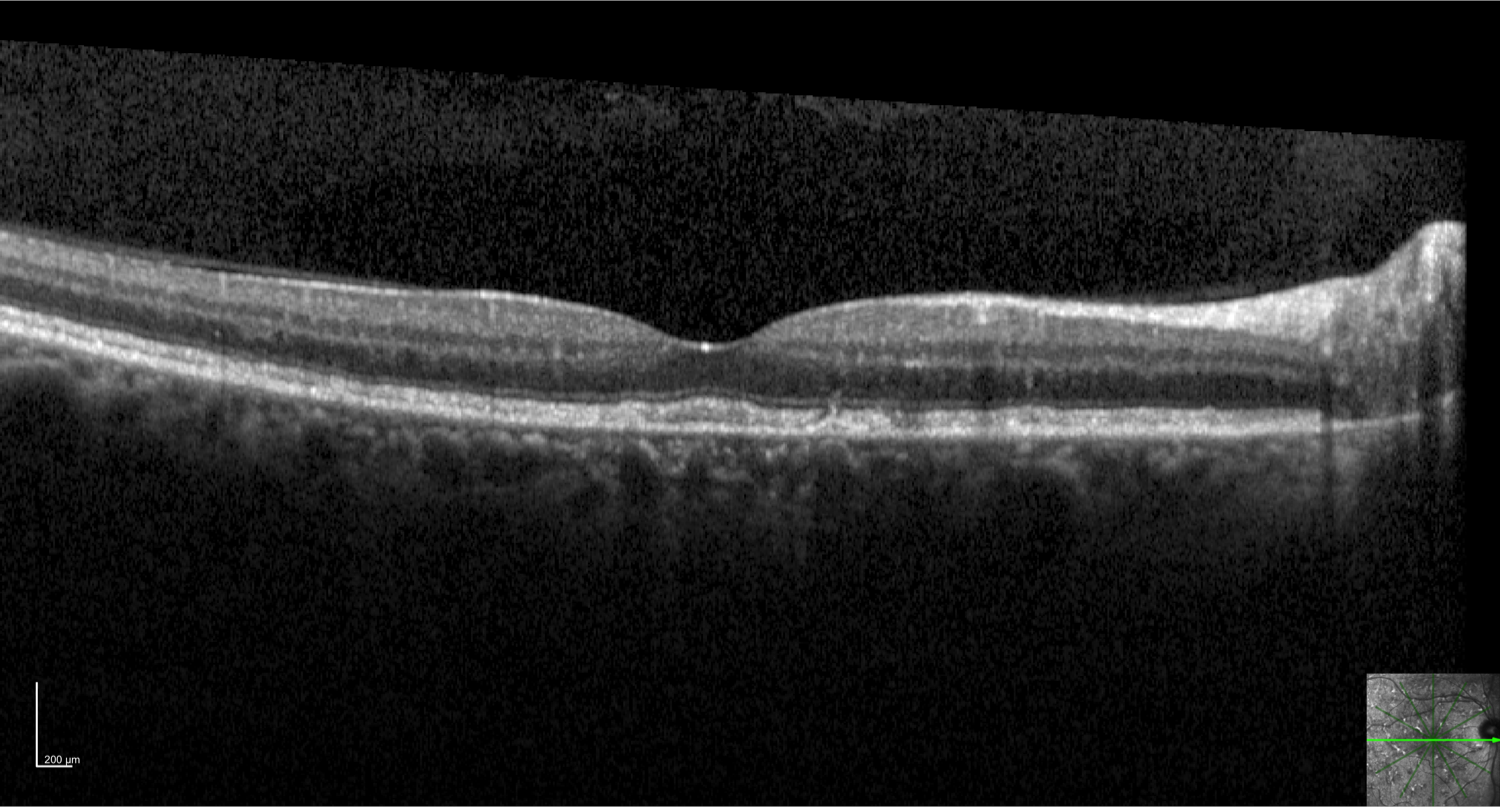

Case 7 is a 63 year old woman with 20/25 vision. She has many similarly affected relatives including one of her parents. Some yellow flecks were first observed in her retinas in her 20’s and there is now an extensive network of reticular yellow deposits throughout the posterior pole.

Optical coherence tomogram of the right eye.